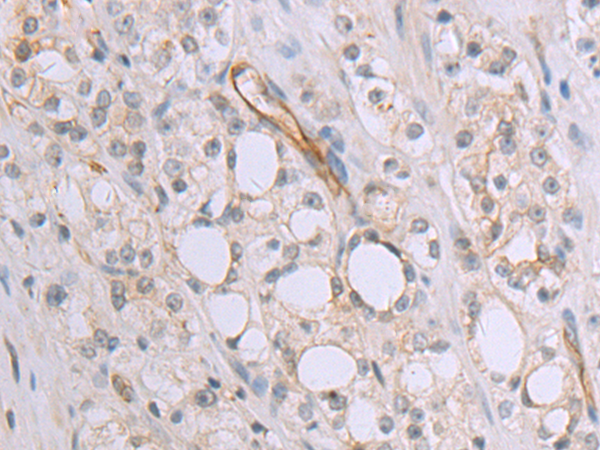

分类: 科研抗体货号: P08307别名: PKB; PTK; CAKB; FAK2; PYK2; CADTK; FADK2; RAFTK应用: WB,IHC反应种属: Human, Mouse, Rat